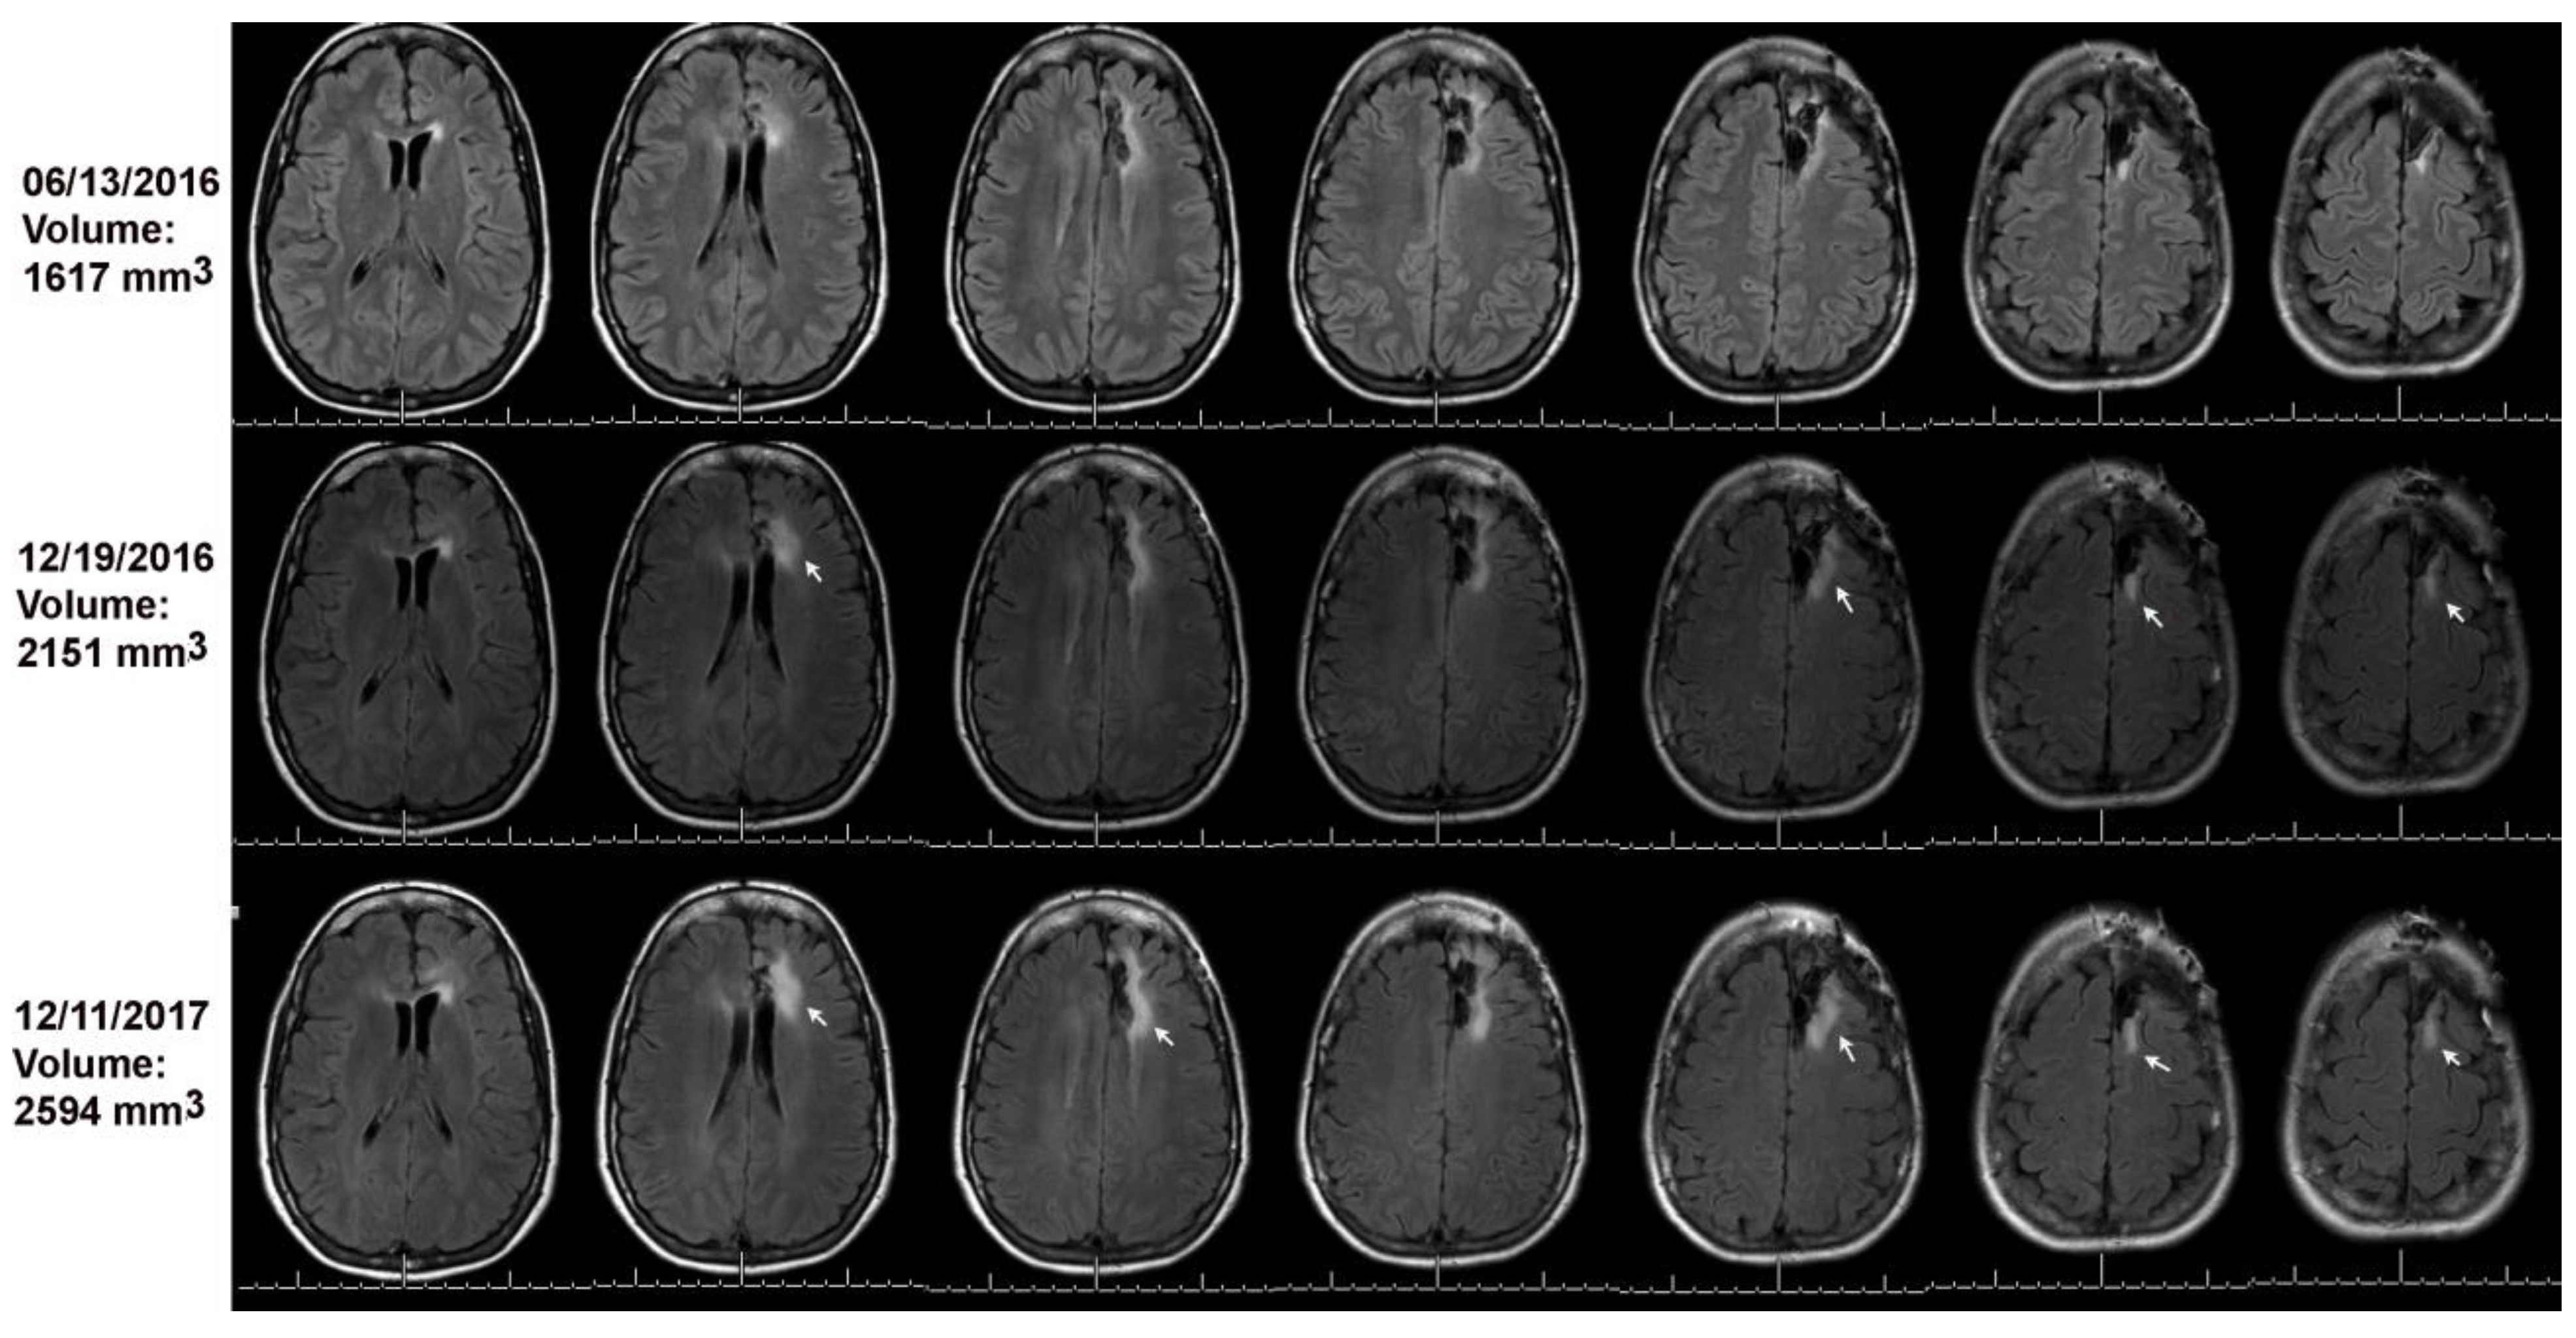

Figure 3. Volumetric analysis combined with the online change-of-point method detected progression on 12/19/2016 (see arrows) as compared to baseline on 06/13/2016. The MRI on 12/11/2017 was read as stable; arrows point to tumor growth as compared to the MRI of 12/19/2016.